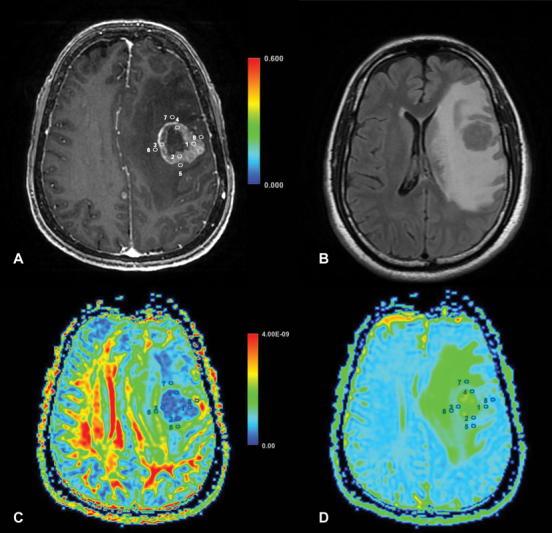

脑肿瘤,包括一系列肿瘤疾病,显著影响患者的发病率和死亡率。区分高级别胶质瘤(HGGs)和孤立性脑转移瘤(SBMs)对于定制临床管理至关重要。传统的结构磁共振成像(MRI)面临着这种分化的挑战,导致了先进成像模式的探索,如扩散张量成像(DTI)。材料和方法在这项前瞻性研究中,41例孤立性增强脑病变患者接受了组织病理学证实的全切除或次全切除。采用3-Tesla MRI扫描仪进行成像,并分析DTI数据的指标,包括平均扩散系数、分数各向异性(FA)、轴向扩散系数、径向扩散系数以及平面、球形和线性(CL)各向异性系数。结果HGG和SBM的瘤周FA和CL差异有统计学意义(p = 0.0217和p = 0.039)。瘤周FA和CL鉴别HGG和SBM的曲线下面积分别为0.2791和0.6984。其他扩散指标无显著差异。结论本研究有助于理解dti衍生的HGG和SBM分化指标。肿瘤周围FA和CL有望作为潜在的鉴别因子,为脑肿瘤患者的临床决策和治疗计划提供见解。未来更大规模的研究和先进的扩散成像技术可以进一步完善这些发现。

Background  Brain tumors, encompassing a spectrum of neoplastic disorders, significantly impact patient morbidity and mortality. Distinguishing between high-grade gliomas (HGGs) and solitary brain metastases (SBMs) is crucial for tailored clinical management. Conventional structural magnetic resonance imaging (MRI) faces challenges in this differentiation, leading to the exploration of advanced imaging modalities such as diffusion tensor imaging (DTI). Materials and Methods  In this prospective study, 41 patients with solitary enhancing brain lesions underwent total or subtotal resection, confirmed by histopathology. Imaging involved a 3-Tesla MRI scanner, and DTI data were analyzed for metrics including mean diffusivity, fractional anisotropy (FA), axial diffusivity, radial diffusivity, as well as planar, spherical, and linear (CL) anisotropy coefficients. Results  Peritumoral FA and CL exhibited significant differences ( p  = 0.0217 and p  = 0.039, respectively) between HGG and SBM. The area under the curve for peritumoral FA and CL in differentiating HGG and SBM were 0.2791 and 0.6984, respectively. No significant differences were observed in the other diffusion metrics. Conclusion  This study contributes to understanding DTI-derived metrics for HGG and SBM differentiation. Peritumoral FA and CL show promise as potential discriminators, offering insights for enhanced clinical decision-making and treatment planning in brain tumor patients. Future research with larger cohorts and advanced diffusion imaging techniques could further refine these findings.